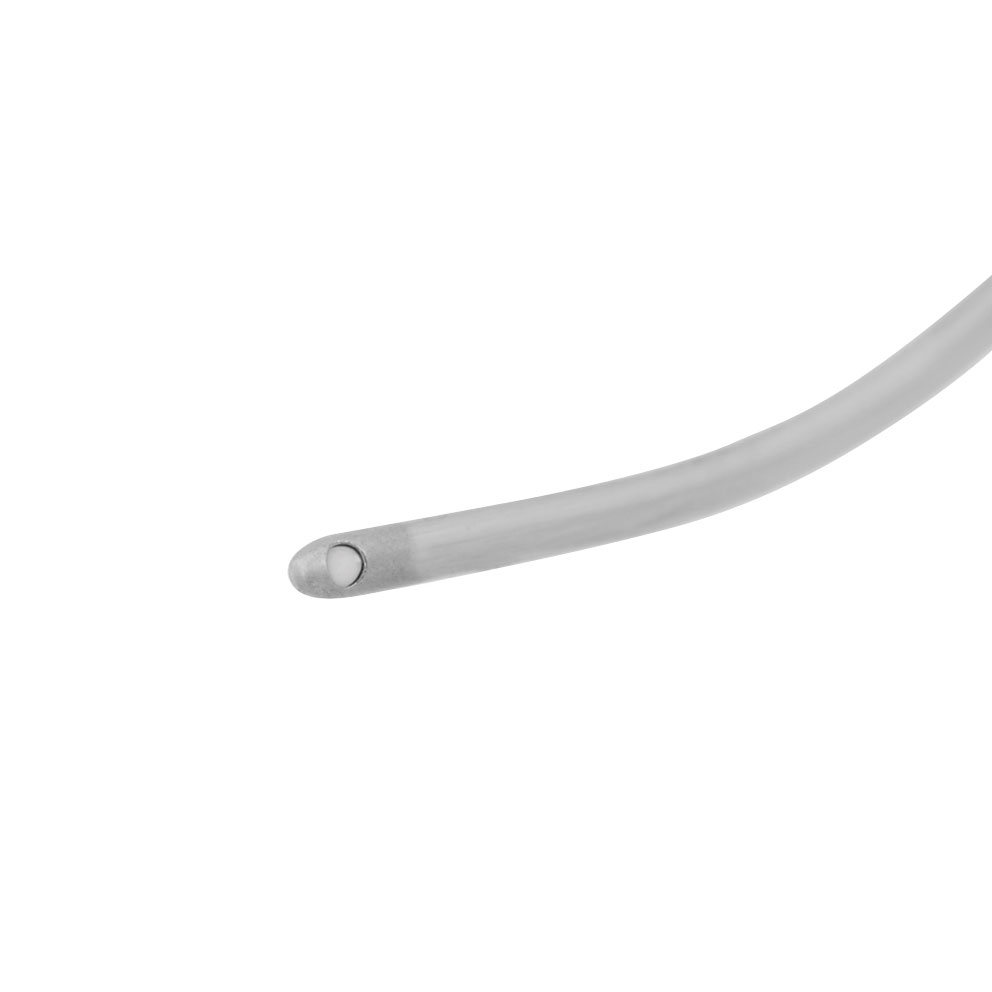

Aspiration Handle for Phacovet 329000, Roughened cannula, 21G

- Kanüle aufgeraut

- 21 G